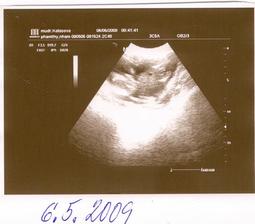

BPD je 2,2 cm,tj. 13+6 tt (Hlavička od ucha k uchu).Prý máme přímo ukázkový miminko.Jsem ale absolutně zmatená,jak je to naše štěstíčko vlastně starý.*****6.5.09 - Dnes jsem byla u dr zase na kontrole,tentokrát šla se mnou dcerka.Tlak super,váha 61,5 kg,takže ofiko 9 kg nahoře.Na dnešní kontrolu UTZ v plánu nebylo,ale když se přišla podívat starší sestra,tak jí paní doktorka miminko ukázala.Ručičky,nožičky,tělíčko a hlavičku a malá byla spokojená jako blecha.I z tohoto kratičkého vyšetření máme fotečku.A dnes bylo UTZ poprvé přes bříško.Sestřičkám jsem darovala 3 zkumavky krve:Na Downův syndrom,rozštěpy a na mojí žádost i na toxoplazmozu,na výsledky si mám volat 15.května..Dostala jsem doporučení na internu,na genetický UTZ do NATALARTu.Další kontrola až 4.6,ach jo.A dnes jsem konečně objednala můj vysněnej přebalováček.*****Od 2.5.2009 - -16+3 tt - naše štěstíčko o sobě konečně začalo dávat vědět.Opírá se mi o bříško zevnitř,pohyby jako takové ještě necítím,ale tlačí mě někdy dost silně.Tlaky se objevují denně,takže jsem si jistá,že je to náš poklad.******13.května 2009 - Jsem nedočkavec,tak jsem už dneska zkusila zavolat na výsledky testů krve a výsledek?ČEKÁME ÚPLNĚ ZDRAVÉ MIMINKO,HURÁÁÁÁÁÁÁÁÁÁÁÁ****** 26.5.2009 - 19+6 tt Dnes mě naše miminko poctilo 1 pořádným kopancem,do dneška to bylo jen takové lechtání a tlaky na břišní stěnu.*****2.6.2009 - Dnes jsme byly na velkém UTZ,vážíme cca 370 g a čekáme zdravou HOLČIČKU.****4.6.09 - Další kontrola u dr.Váha 66 kg,tzn +13,5 kg.Jaterní testy i laboratoř v pořádku,tlak super.Jen mám bílkovinu v moči.*****16.6.2009 - Dnes jsem byla na testu na cukrovku.No a jak to dopadlo,tak moc mi to chutnalo,že jsem se pozvracela.Doktorka mě na to naštěstí znova nepožene.Je fakt zlatá.*****Další poradna 4.7.2009 - 25 tt **** 28.6.2009 - 24+1 tt - Dneska se naše malinká rozkopala tak,že si začínám myslet,že bude kopat za nároďák.Už to nejsou ty ojedinělé kopance,ale kope do mě třeba 2 hodiny v kuse.Někdy je to nepříjemné,ale aspoň o cácorce vím a už se tolik nestrachuju,jestli je v pořádku.*****Kontrola ve 25 tt -2.7.09 - Tak jsem sice dneska na kontrole sice dostala prenatal box,ale radost z toho vůbec nemám.Mám asi nejspíš zánět močáku,protože mám nějakou potvoru v moči,takže se mám prolejvat urologickým čajem.